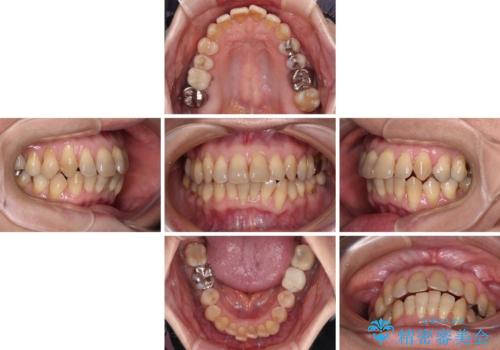

- 上下前歯のデコボコと、奥歯の銀歯を気にして来院された患者様です。

仕事柄あまり目立つ装置は付けることは避けたいとのことで、インビザラインによるマウスピース矯正を行うこととしました。

概ね歯列が整ったところで銀歯の全てをセラミッククラウンなどに置き換え、その後インビザラインを1セット使用して仕上げていくこととしました。

矯正治療の後半にはホワイトニングもされ、スッキリした口元に仕上げることができました。